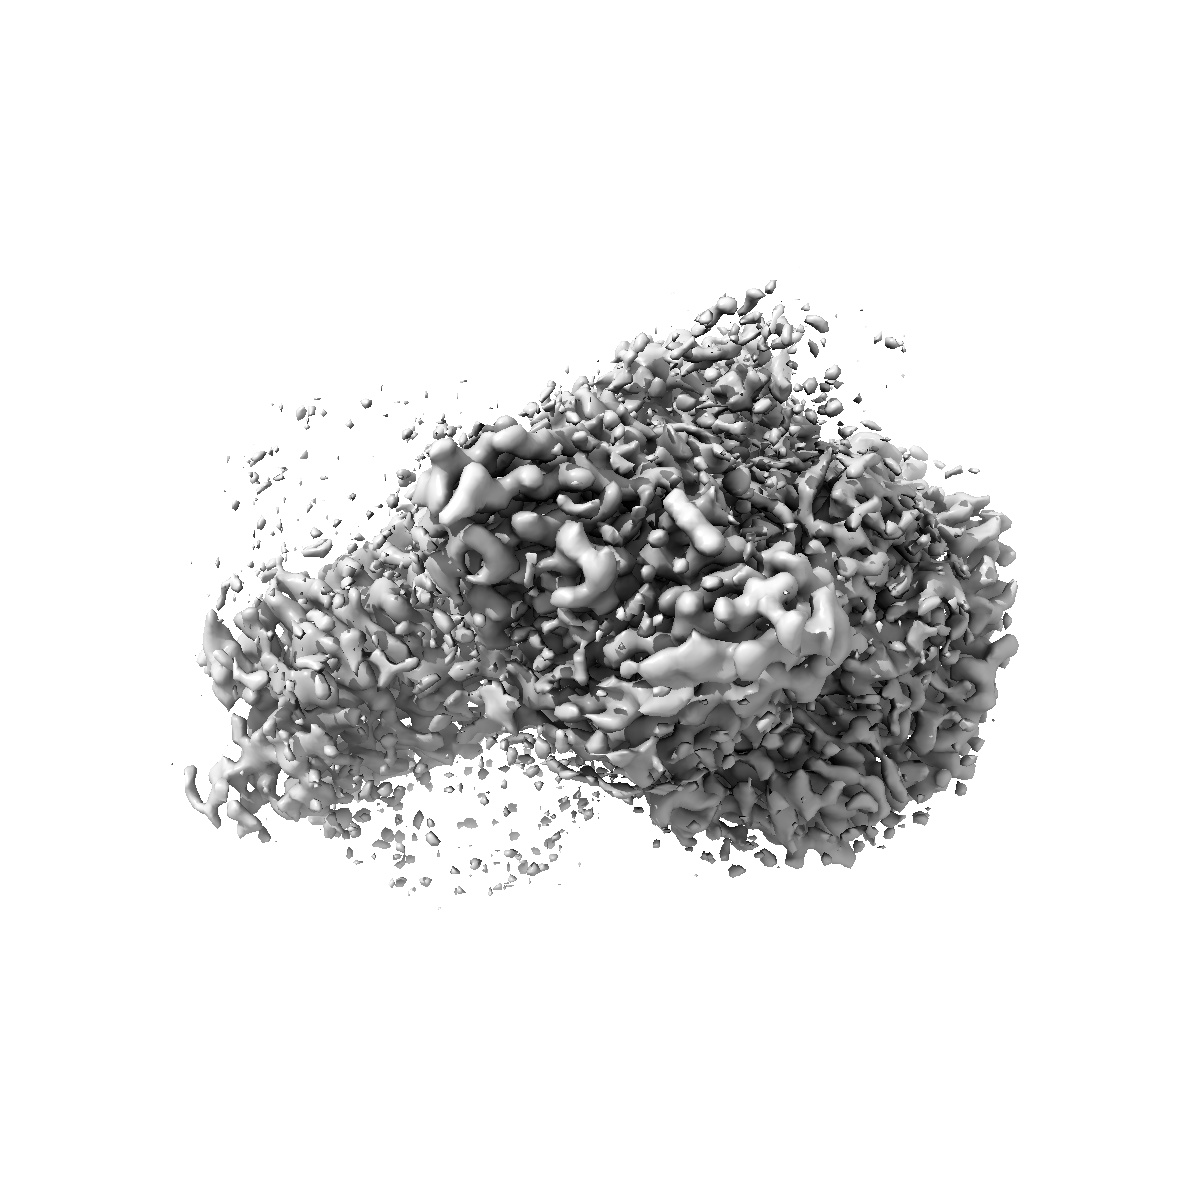

Cryo-EM structure of the anamorelin-bound ghrelin receptor and Gq complex

Single-particle2.9 Å

Sample: Anamorelin-bound ghrelin receptor in complex with Gq